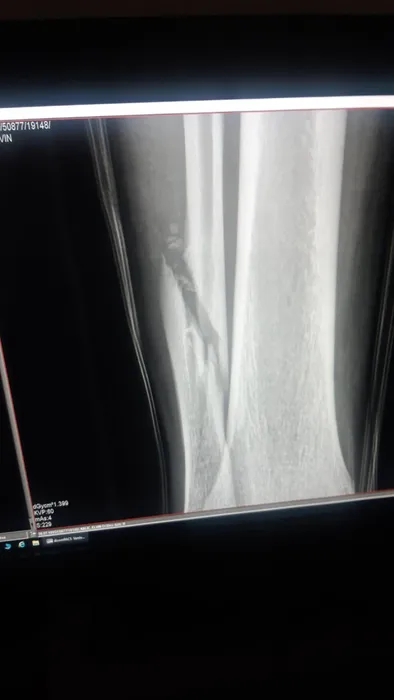

A patra accidentare gravă în 3 ani a lui Koljic! Bosniacul are fractură de peroneu şi va rata tot acest sezon | FOTO